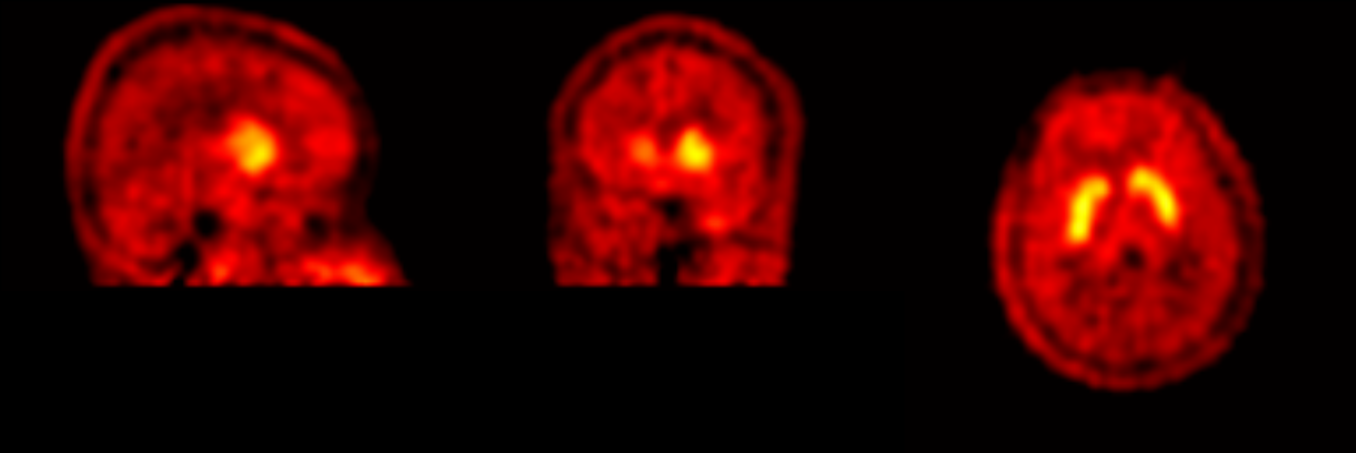

Following the meeting with Giovanna to review the first version of the FDOPA PET Imaging leaflet, Gill worked on the revisions needed to create the second version. Giovanna had provided three different photographic images of PET scans:

Gill experimented with drawing the rainbow colour-scheme and the blue-green colour scheme PET scans, as the red colour scheme is not as visually appealing and would not work as well with the existing illustrations. The scans will have to be placed on a black background (as in the header image of this post) to look their best, and to match how the scan results appear in the PET imaging software.